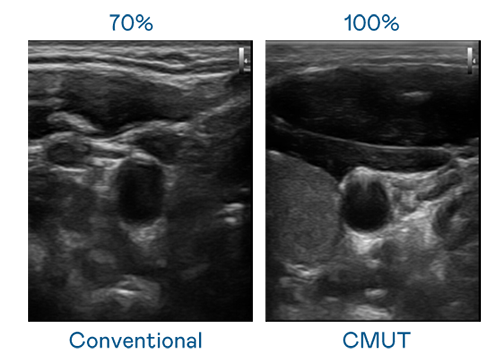

CMUT 技术是一种用电容式微机电元件来产生超音波讯号的技术。与传统 PZT 压电式技术相比,CMUT 频宽增加 30%,更宽频的超音波讯号让影像解析度大幅提升,是实现高影像品质医疗超音波扫描、促进精准医疗发展的关键技术。

超音波影像的解析度高低,首先取决于探头能发出的讯号频宽。Top1体育 CMUT 可提供高清晰的超音波讯号,提供高频宽、高灵敏度、影像纹理细节更高的超音波影像,协助医护人员缩短影像判读时间及利用精准的医疗影像进行诊断。